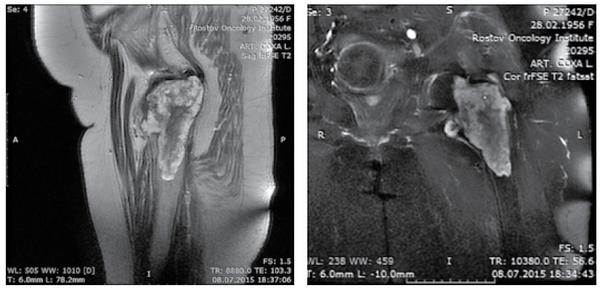

Опухоли после мрт

Опухоли после мрт 113 фото